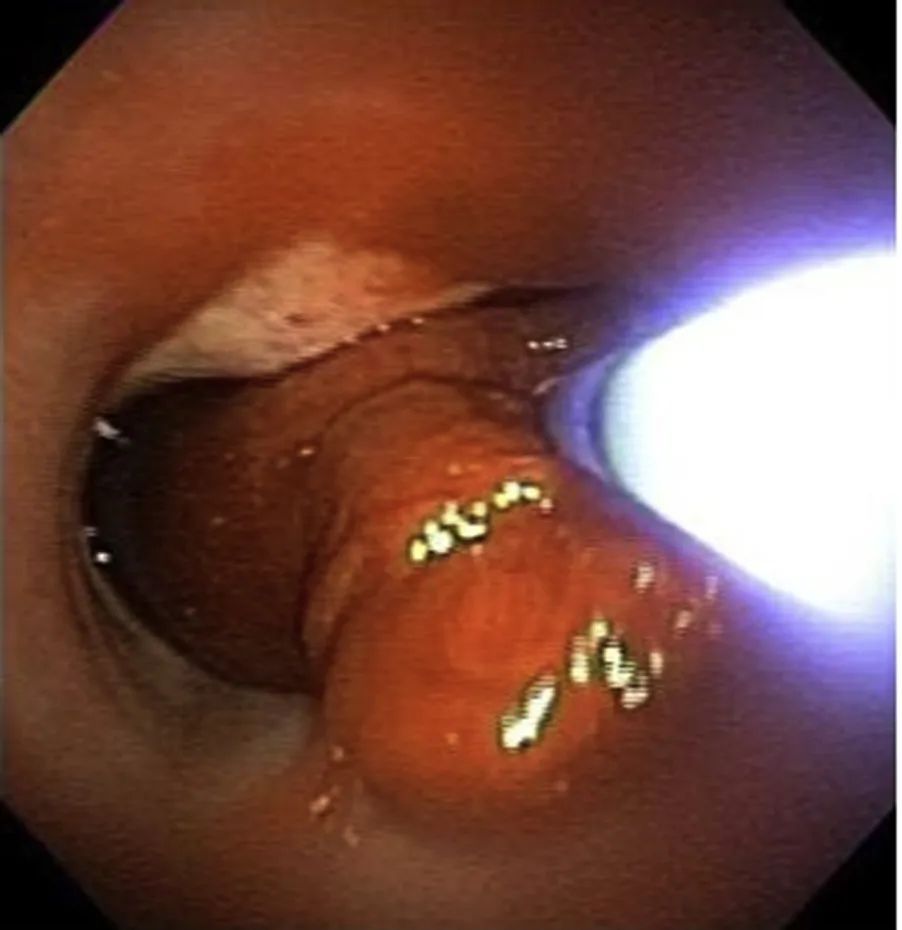

建立人工气道。由于大部分大咯血来源于气道损伤,因此通过胸部影像学检查或支气管镜检查(通常使用硬质支气管镜)明确出血部位将为后续的治疗提供便利。

稀释液都被认为会引起局部血管收缩,在无严格证据的情况下被广泛使用。使用冰生理盐水已是较为普遍的做法,但是滴注的冰生理盐水量通常较小。与冰生理盐水相比,支气管内使用肾上腺素的疗法受到质疑,尤其是对冠状动脉痉挛和心律失常

的患者。